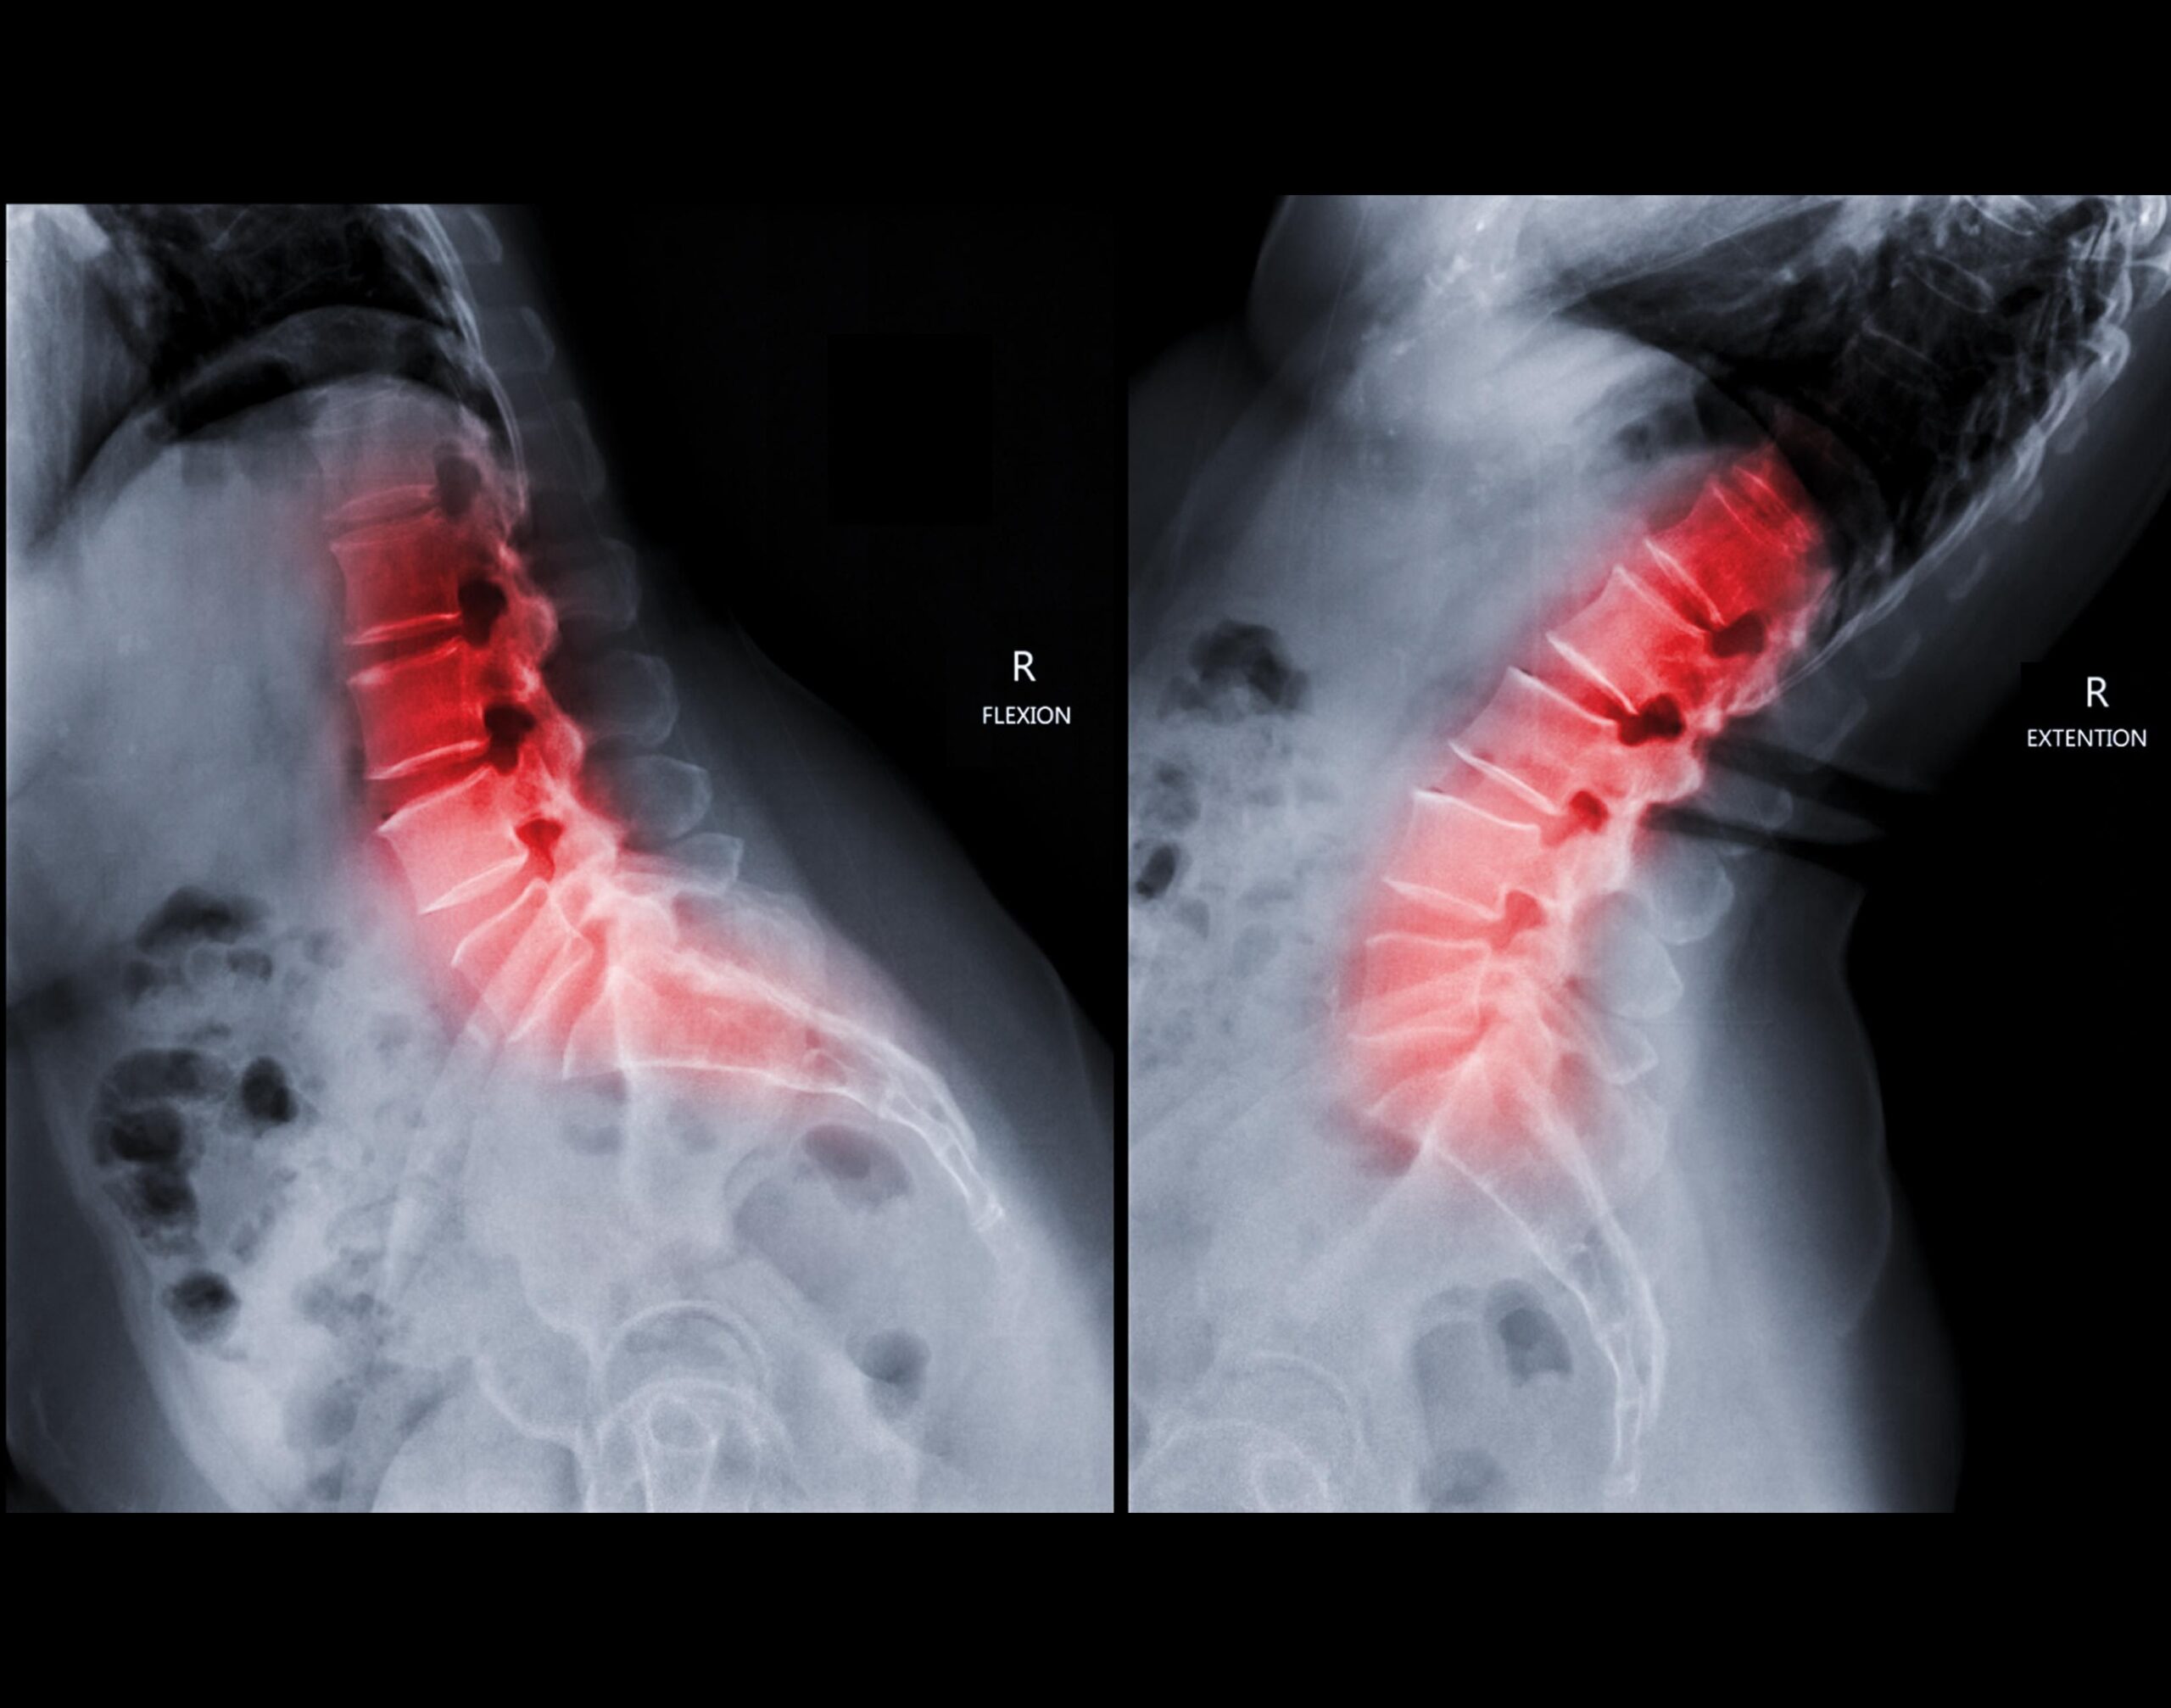

The Lumbar Spine Flexion and Extension Views are dynamic X-ray projections used to assess the stability and mobility of the lumbar vertebrae. In the flexion view, the patient bends forward, curling the spine, while in the extension view, the patient leans backward, arching the spine. These views help detect abnormal motion, segmental instability, or post-surgical changes such as hardware failure or non-union in spinal fusion. They are particularly valuable in evaluating conditions like spondylolisthesis, ligament injuries, and degenerative disc disease, providing insight into how the spine moves under stress.

Lumbar spine Flexion/Extension